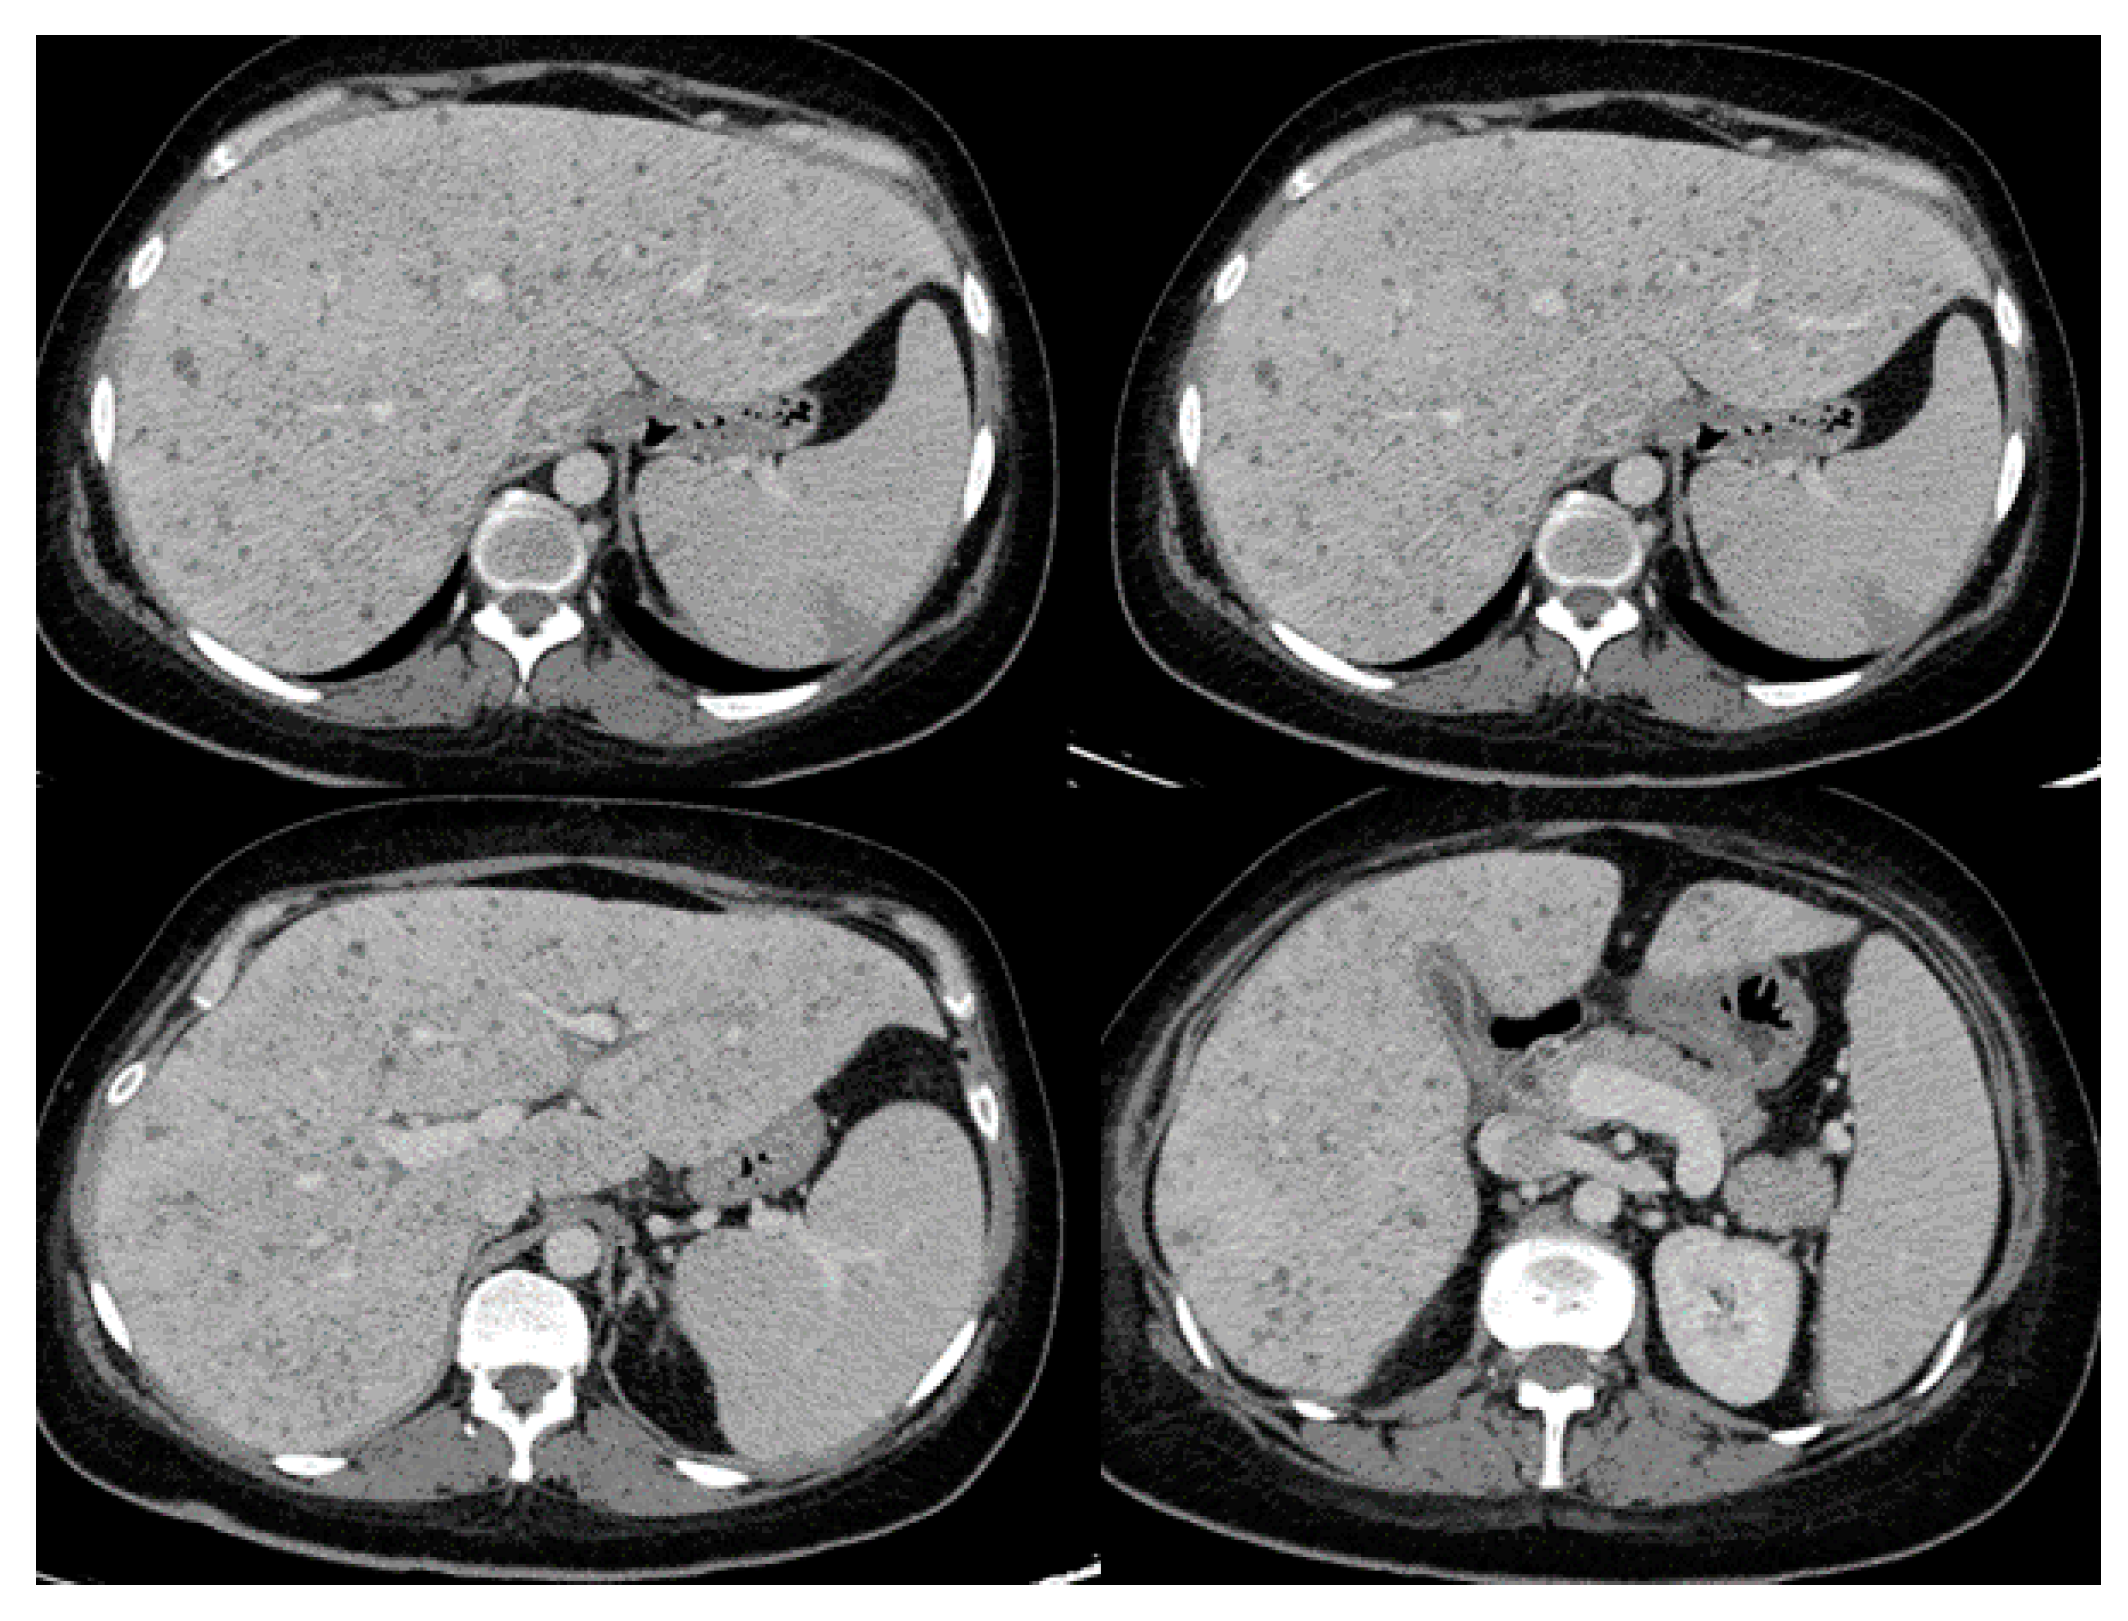

| Presenting Symptoms | Radiographic Findings | |

| Pulmonary Involvement [17,27,29,30,35,50] |

|

| Intraabdominal and genitourinary Involvement [15,17,19,27,28,29,30,34,45,52] |